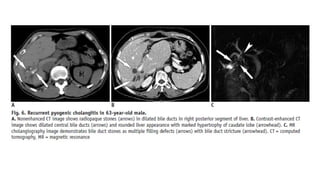

Recurrent Pyogenic Cholangitis

• Recurrent pyogenic cholangitis is a progressive biliary disease characterized by recurrent

episodes of cholangitis and intrahepatic pigmented stones . RPC is prevalent in Asian countries

and equally affects patients of both sexes

• These patients typically present with abdominal pain, fever, and jaundice (the Charcot triad) and

often have a history of recurrent episodes. The laboratory tests in RPC may demonstrate

leukocytosis and elevated serum bilirubin

• Although the exact pathogenesis of RPC is unknown, strong associations with parasitic

infestation such as Clonorchis sinensis or Ascaris lumbriocoides, portal bacteremia, and

malnutrition. Chronic recurrent infection of the bile ducts is thought to induce biliary stricture,

bile stasis, and pigmented biliary stones.

• The diagnosis of RPC is based on the demographic background, as well as the clinical and

imaging features. Abdominal US in RPC shows bile duct dilatation with increased periportal

echogenicity. The intrahepatic bile duct stones can show various degrees of echogenicity and

posterior shadowing . CT in RPC demonstrates disproportional dilatation of central intrahepatic

ducts and extrahepatic bile ducts with nondilated or minimally dilated peripheral ducts, leading

to decreased arborization and abrupt tapering of bile ducts

Recurrent Pyogenic Cholangitis •Recurrent pyogenic cholangitis is a progressive biliary disease characterized by recurrent episodes of cholangitis and intrahepatic pigmented stones . RPC is prevalent in Asian countries and equally affects patients of both sexes • These patients typically present with abdominal pain, fever, and jaundice (the Charcot triad) and often have a history of recurrent episodes. The laboratory tests in RPC may demonstrate leukocytosis and elevated serum bilirubin • Although the exact pathogenesis of RPC is unknown, strong associations with parasitic infestation such as Clonorchis sinensis or Ascaris lumbriocoides, portal bacteremia, and malnutrition. Chronic recurrent infection of the bile ducts is thought to induce biliary stricture, bile stasis, and pigmented biliary stones. • The diagnosis of RPC is based on the demographic background, as well as the clinical and imaging features. Abdominal US in RPC shows bile duct dilatation with increased periportal echogenicity. The intrahepatic bile duct stones can show various degrees of echogenicity and posterior shadowing . CT in RPC demonstrates disproportional dilatation of central intrahepatic ducts and extrahepatic bile ducts with nondilated or minimally dilated peripheral ducts, leading to decreased arborization and abrupt tapering of bile ducts